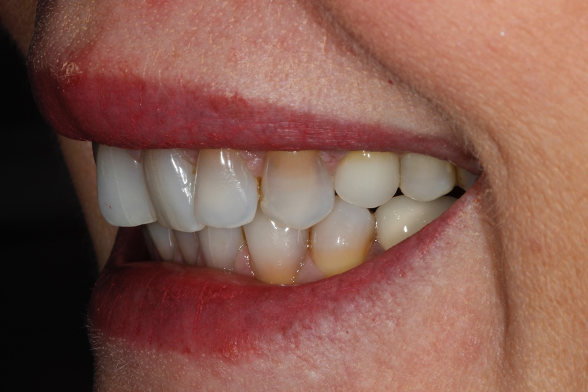

If all of these considerations are taken into account with this case, we can see that the upper right central incisor would be subject to significant tooth reduction (Figures 1b and 1c) and the risk of iatrogenic pulpal death would be increased. Even with immediate dentine sealing and other protective practices adopted.

So, prior to a hygiene work up, the patient was then assessed from an orthodontic perspective for short-term pre-restorative orthodontics. This was to improve tooth position (Figures 2 a,b and c) and allow for a less destructive tooth preparation.